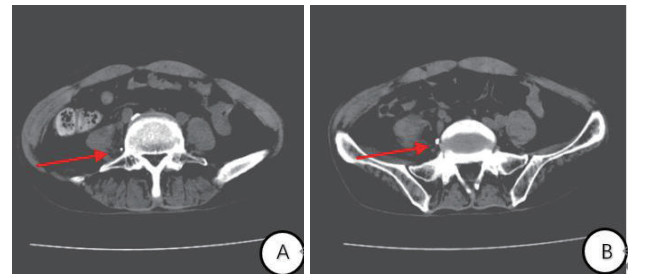

1.2 诊治经过及临床转归入院后给予高压氧治疗每日2 h(2.5 ATA,烟台豪特医用空气加压氧仓)、呼吸机辅助呼吸、营养脑细胞、抗感染等综合治疗。为建立肠外营养通路,采用Seldinger穿刺法行右侧股静脉双腔导管置入术,导管型号为:河南驼人牌3-7Fr-20 cmⅡ型。先后给予静脉泵入去甲肾上腺素、20%脂肪乳、复方氨基酸等药物治疗。入院后7 d出现反复低热,体温多波动在37.5~38℃之间,查血PCT 0.02 ng/mL、CRP 16 mg/L,局部分泌物和血培养未见异常。换药时可见导管皮肤处周围有黄色分泌物,静滴进口左氧氟沙星注射液0.5 g/d后无明显好转。入院后12 d复查CT提示:腹膜后积液,积液主要位于腰大肌和腰椎间隙,股静脉导管异位(图 1)。遂拔出中心静脉导管,B超定位下经皮穿刺引流腹膜后积液(图 2),可见淡黄色液体,共引流600 mL,患者2 d后体温逐渐恢复正常。

| 图 2 腹部CT横断面(A, B)股静脉导管尖位置 |